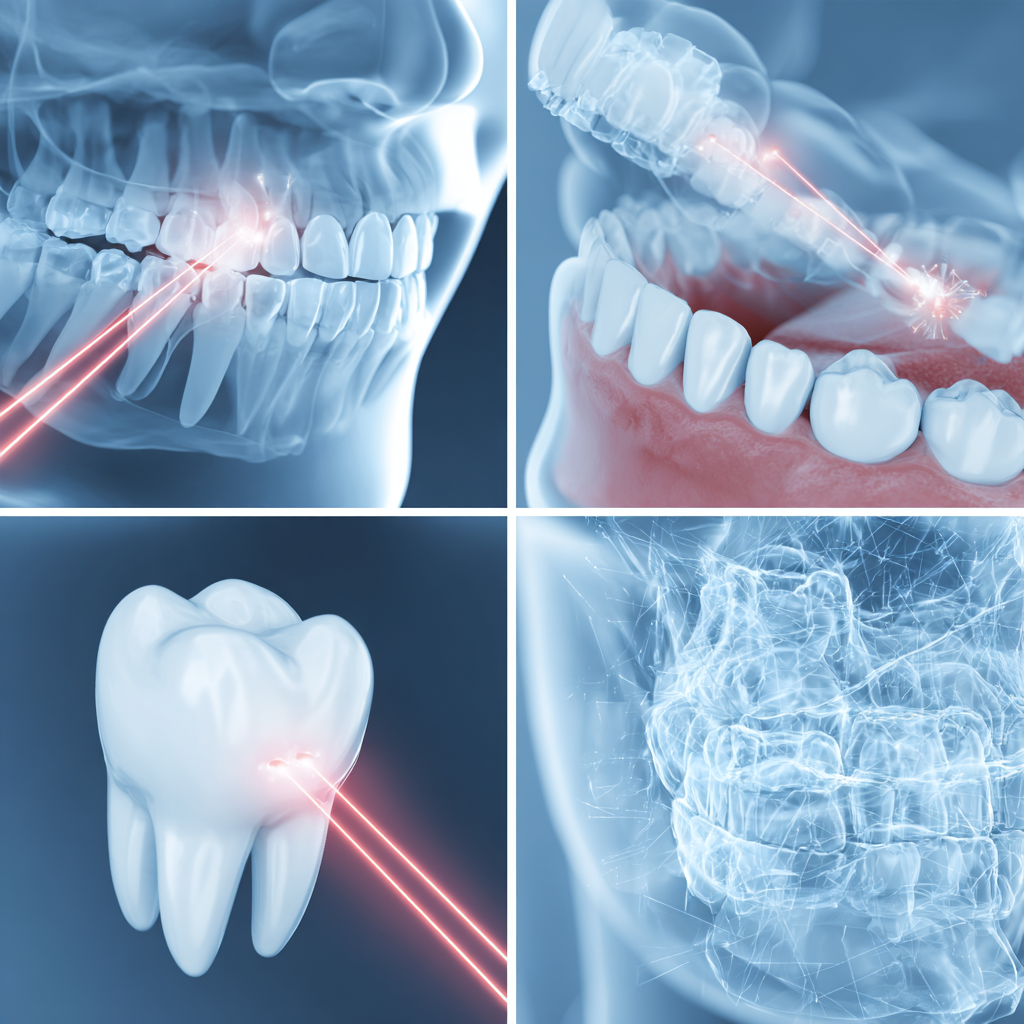

Dental laser treatments

What Are Dental Laser Treatments?

Dental laser treatments are advanced procedures that use focused light energy to treat a variety of dental conditions quickly, precisely, and with minimal discomfort. Lasers can be used for soft tissue procedures—such as gum reshaping, treating gum disease, and removing oral lesions—as well as for hard tissue treatments like cavity removal and teeth whitening. At Ibdaa Dental Clinic, we utilize cutting-edge laser technology to provide minimally invasive care, reduce healing time, and enhance your overall dental experience.